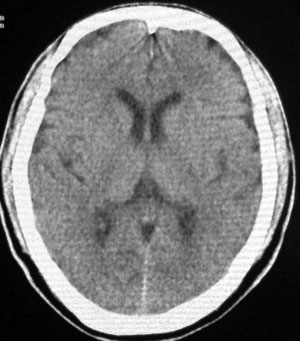

男性,65岁,头疼。 看看这大脑镰,ct值约83hu .

头痛与大脑镰钙化应该关系不大。

没有问题的!老年人!头痛的原因很多!大脑镰的钙化这样年龄的病人可以不提示!

大脑镰钙化,应该没有疑问吧